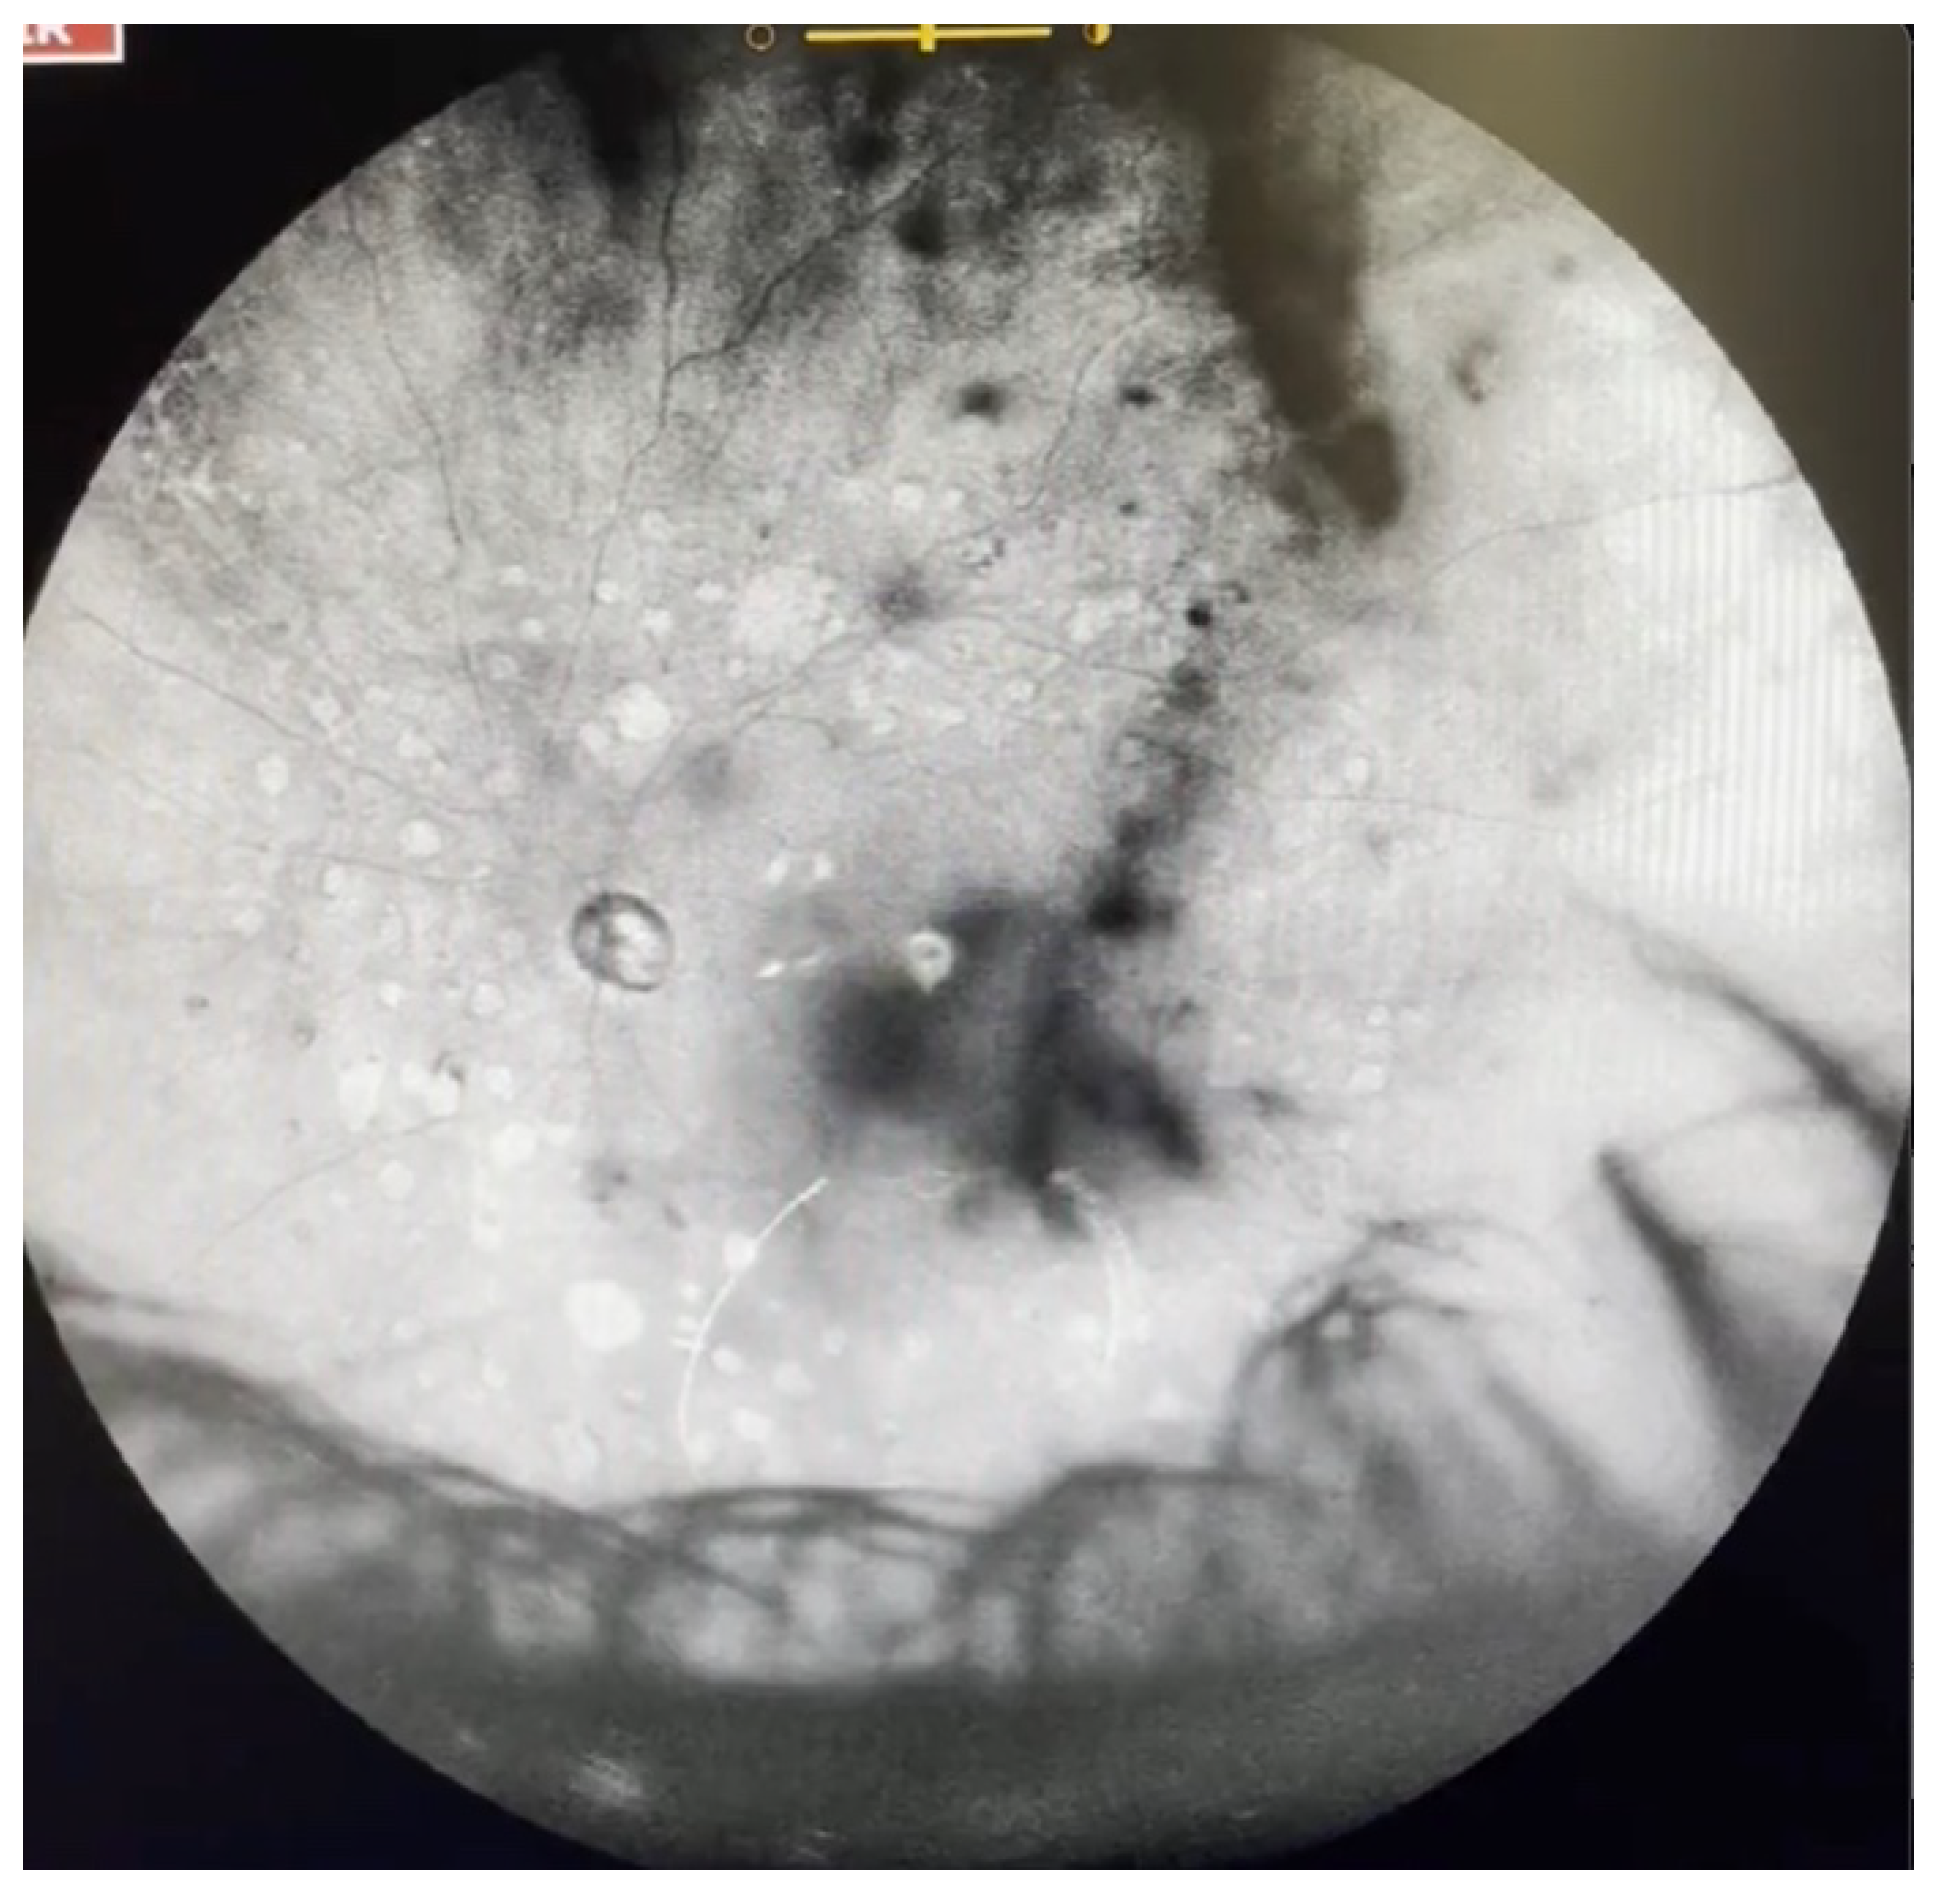

Figure 9.

Ultra-widefield IRcSLO image of an eye with Grade 5 vitreous floaters secondary to vitreous hemorrhage in a patient with history of central retinal vein occlusion that was treated with laser photocoagulation. Dense shadows are observed within the macular area in the primary gaze. See also Video S9.